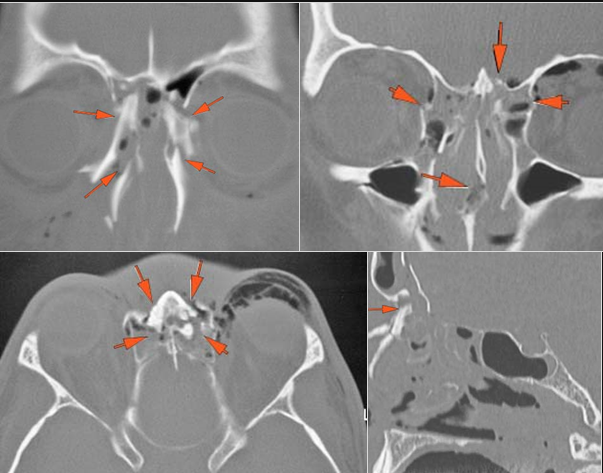

Right Temporal Bone

Left Temporal Bone